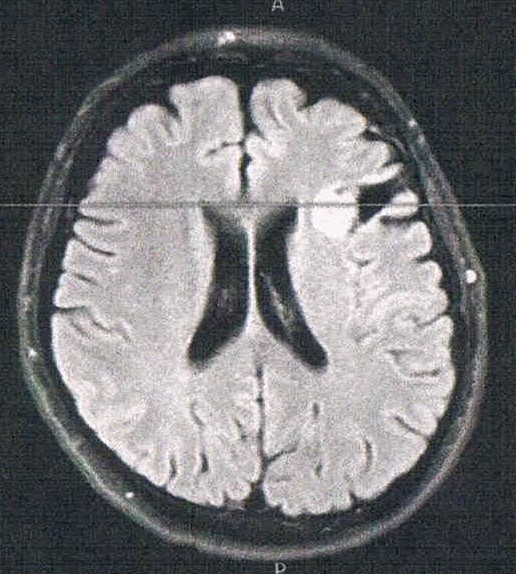

- びまん性星細胞腫グレード2(悪性転化しやすい腫瘍)

- 今回のは白く映って大きく見えるが変化は無し。

- 珍しく前後方向の断面を見せてくれた